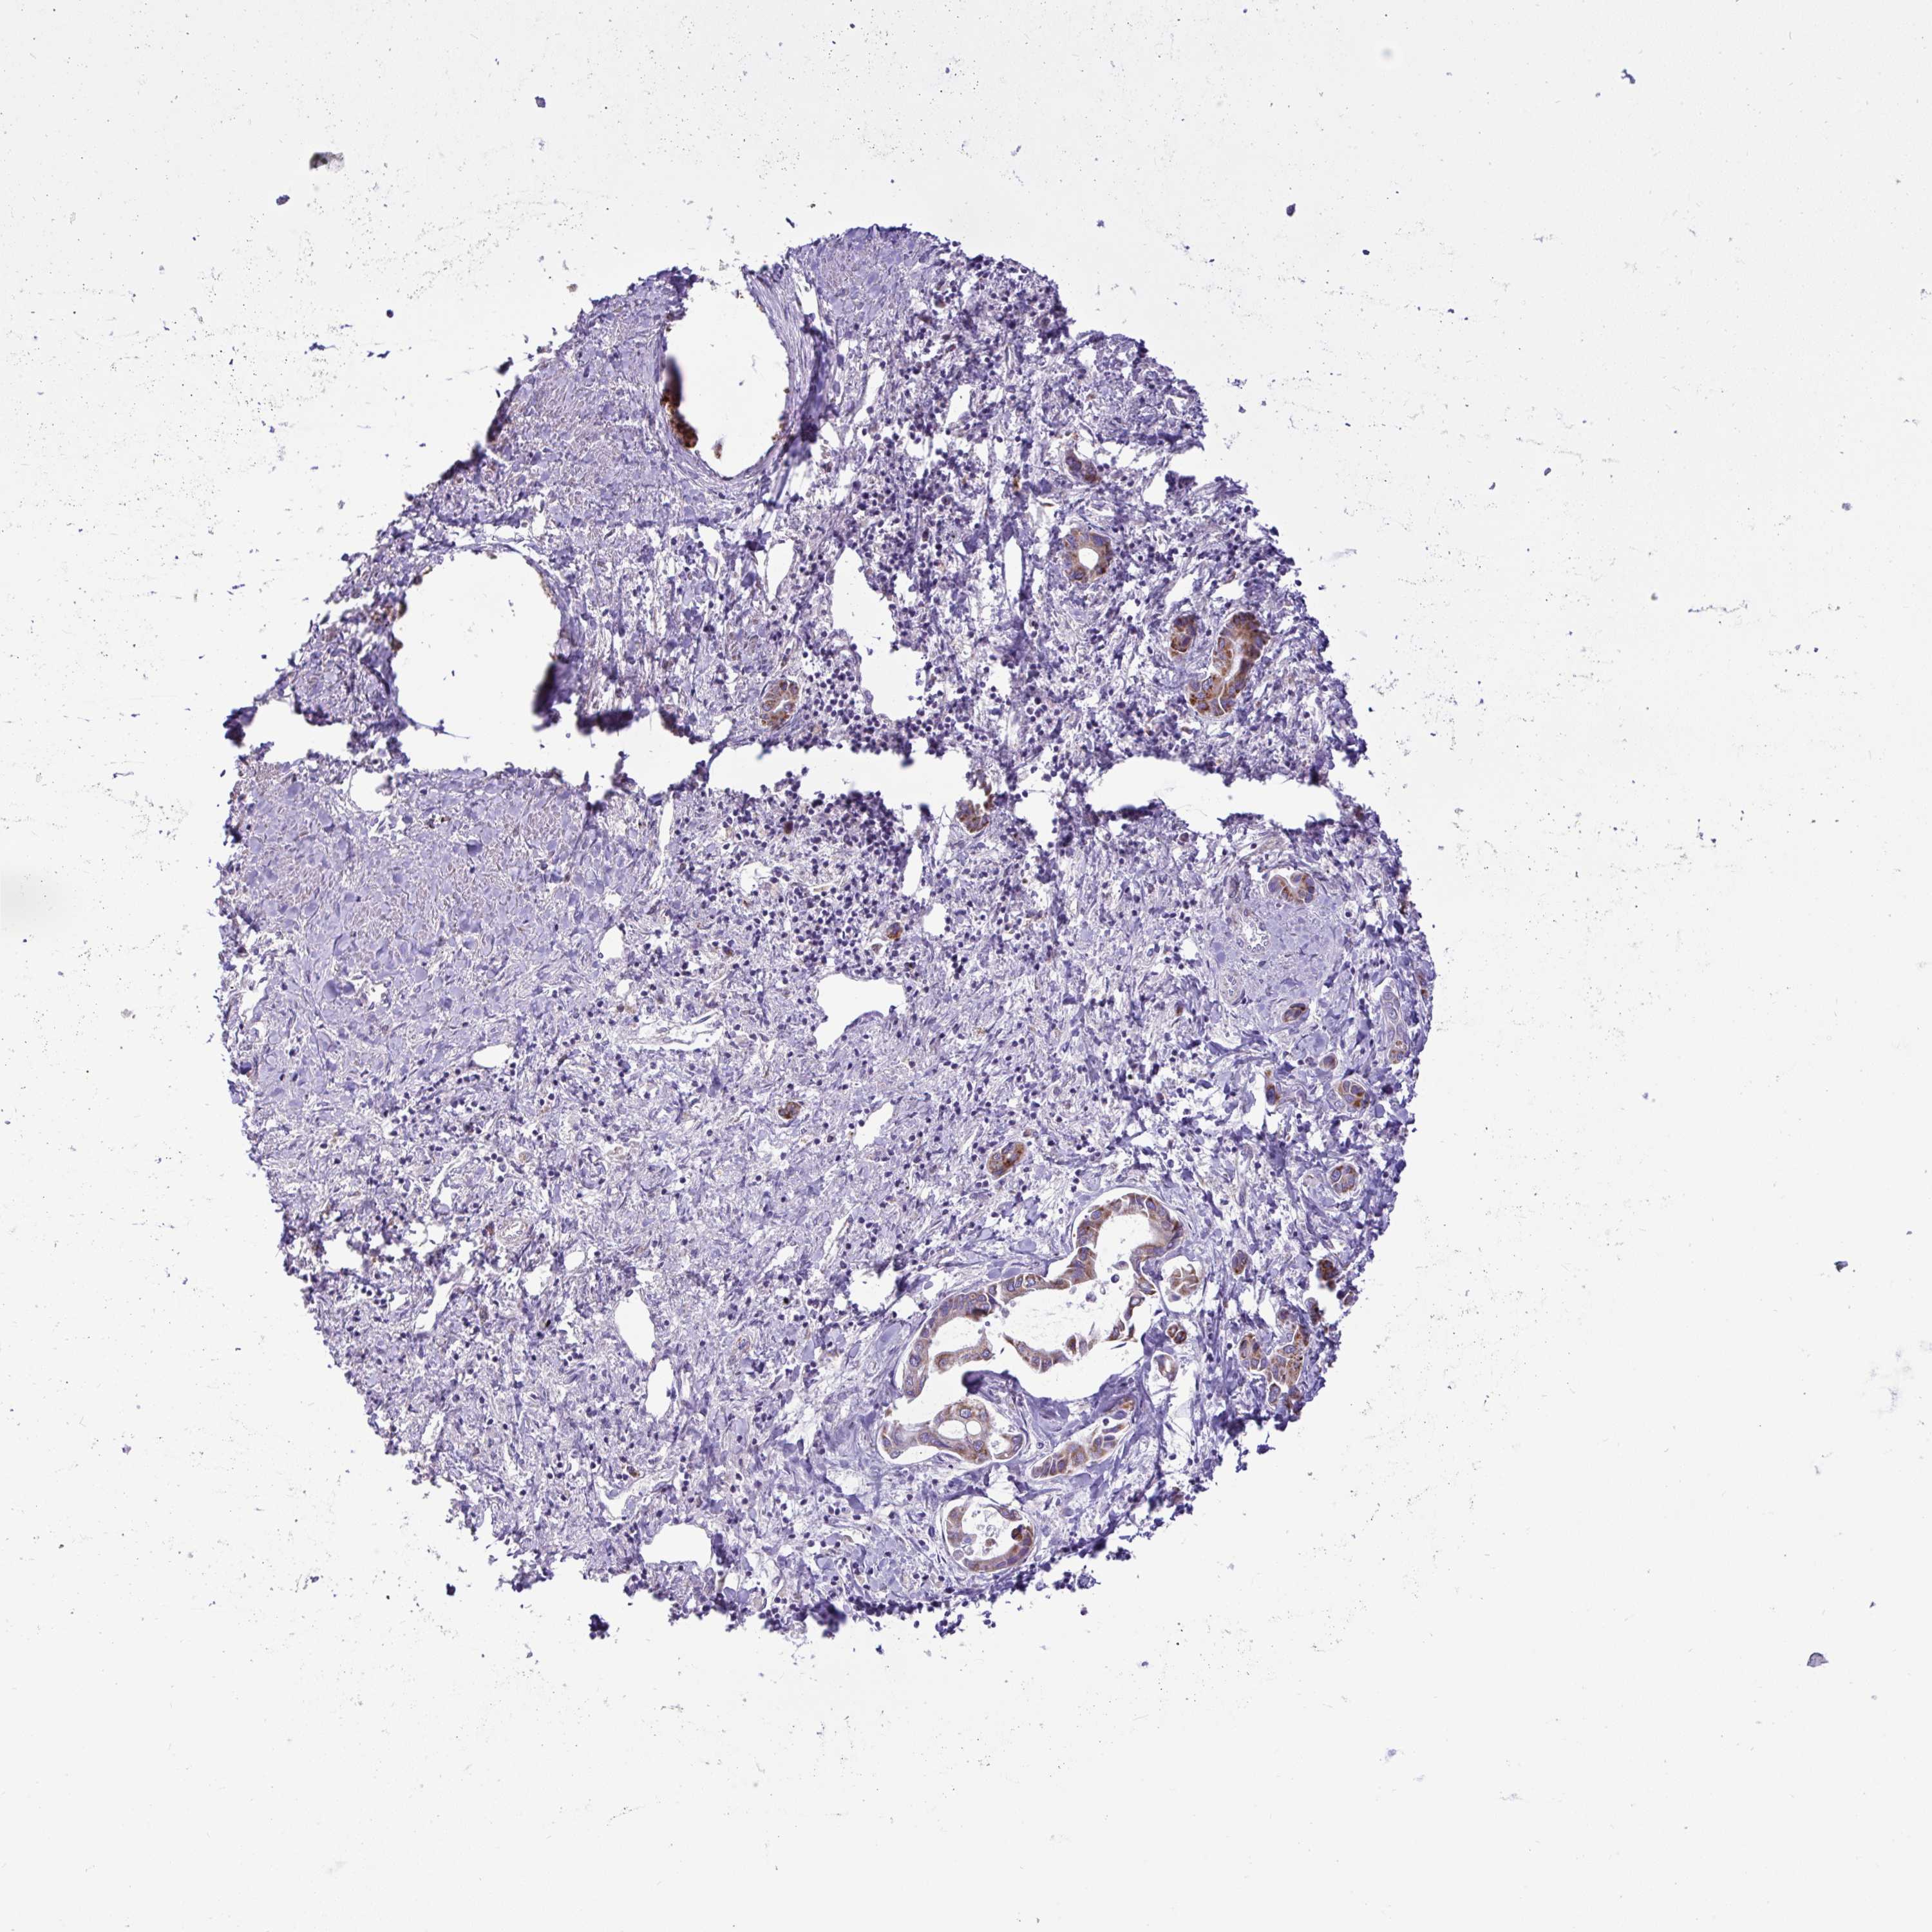

LIVER CANCER - Protein expressioni

A mouse-over function shows sample information and annotation data. Click on an image to view it in a full screen mode. Samples can be filtered based on level of antibody staining by selecting one or several of the following categories: high, medium, low and not detected. The assay and annotation is described here.

Note that samples used for immunohistochemistry by the Human Protein Atlas do not correspond to samples in the TCGA dataset.

Antibody stainingi

Antibody staining in the annotated cell types in the current human tissue is reported as not detected, low, medium, or high, based on conventional immunohistochemistry profiling in selected tissues. This score is based on the combination of the staining intensity and fraction of stained cells.

Each image is clickable and will lead to virtual microscopy that enables deeper exploration of all samples and also displays staining intensity scores, fraction scores and subcellular localization as well as patient and tissue information for each sample.

Antibody HPA057267

Antibody HPA058086

Staining

High

Medium

Low

Not detected

Intensity

Strong

Moderate

Weak

Negative

Quantity

>75%

75%-25%

<25%

None

Location

Nuclear

Cytoplasmic/membranous

Cytoplasmic/membranous,nuclear

Carcinoma, Hepatocellular, NOS

Cholangiocarcinoma